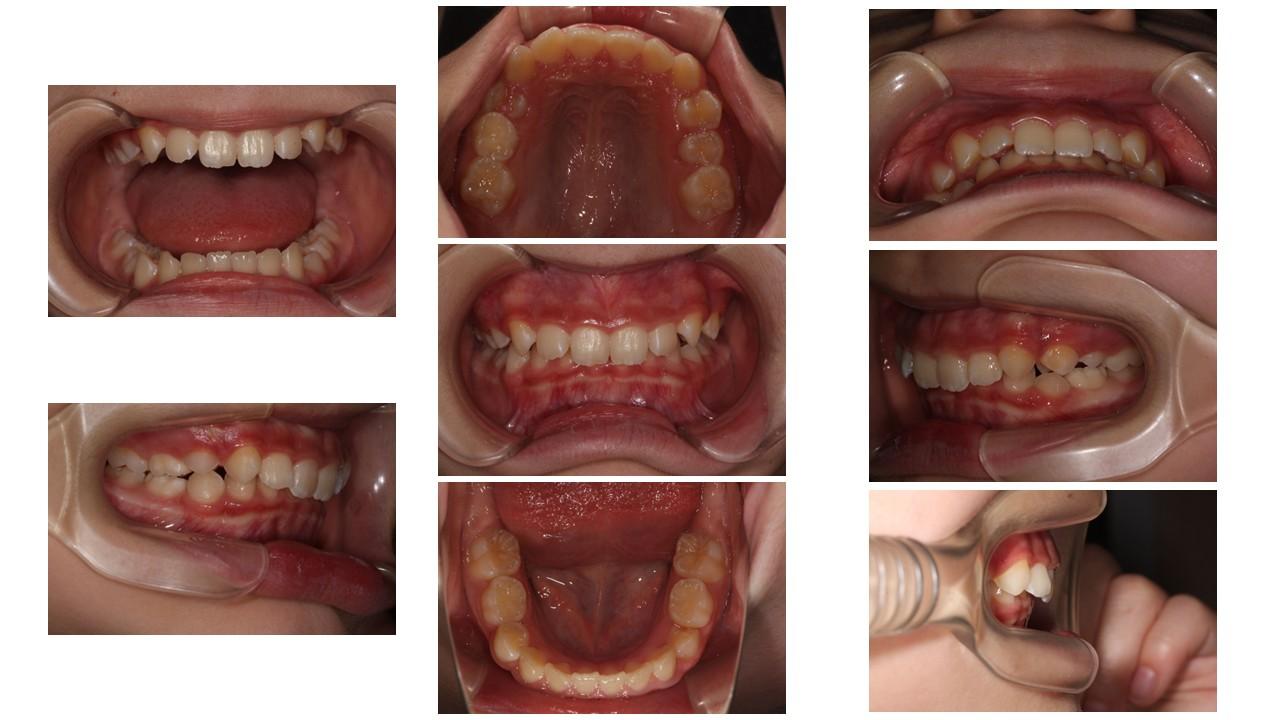

「叢生」は、一般的に「乱ぐい歯(らんぐいば)」「八重歯(やえば)」「ガタガタの歯並び」などと呼ばれる状態で、日本人に非常によく見られる不正咬合(ふせいこうごう:良くない噛み合わせ)です。

<叢生の状態>

顎(あご)の骨の大きさに対して、歯のサイズが大きすぎたり、歯が並ぶスペースが不足していたりするために、歯がデコボコに重なり合って生えている状態を指します。